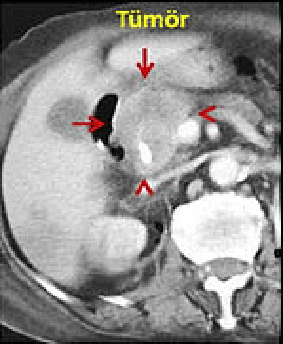

Pankreas başı kanseri (kırmızı oklar) olan hastamıza 2 probla kriyoablasyon yapılıyor.

İşlem sırasında çekilen tomografide kriyoabalasyonun oluşturduğu buztopu izleniyor.